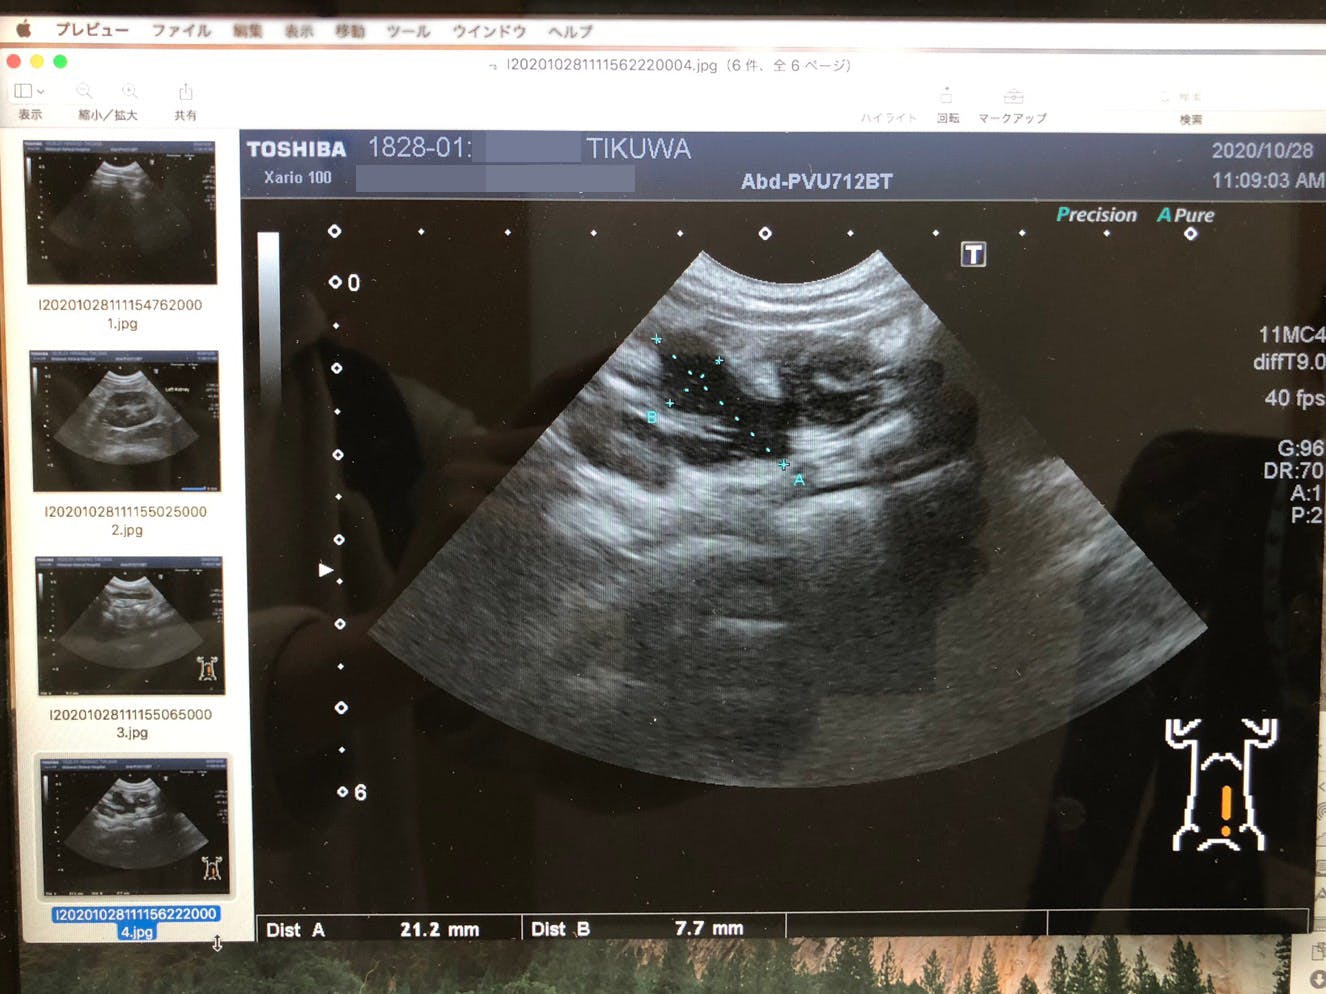

10月20日、動物病院に連れていき血液検査とエコーによる検査をすると、 血液検査で異常があり、腸管に炎症症状がみられることが発覚しました。

血液検査で、高グロブリン血症と肝疾患が確認されました。また、エコー検査で腸管の炎症が見られました。この結果を受けて、すぐに採取した血液をFIPの検査に出しました。

10月28日

Mutianを処方していただける病院を見つけたので、急遽予約を取りその病院へ行きました。

そして、この日行って頂いた検査の結果、肉芽腫の発見により「ドライタイプ」であるという事が分かりました。

また、貧血が進んでいることからFIPの中期であると告げられました。